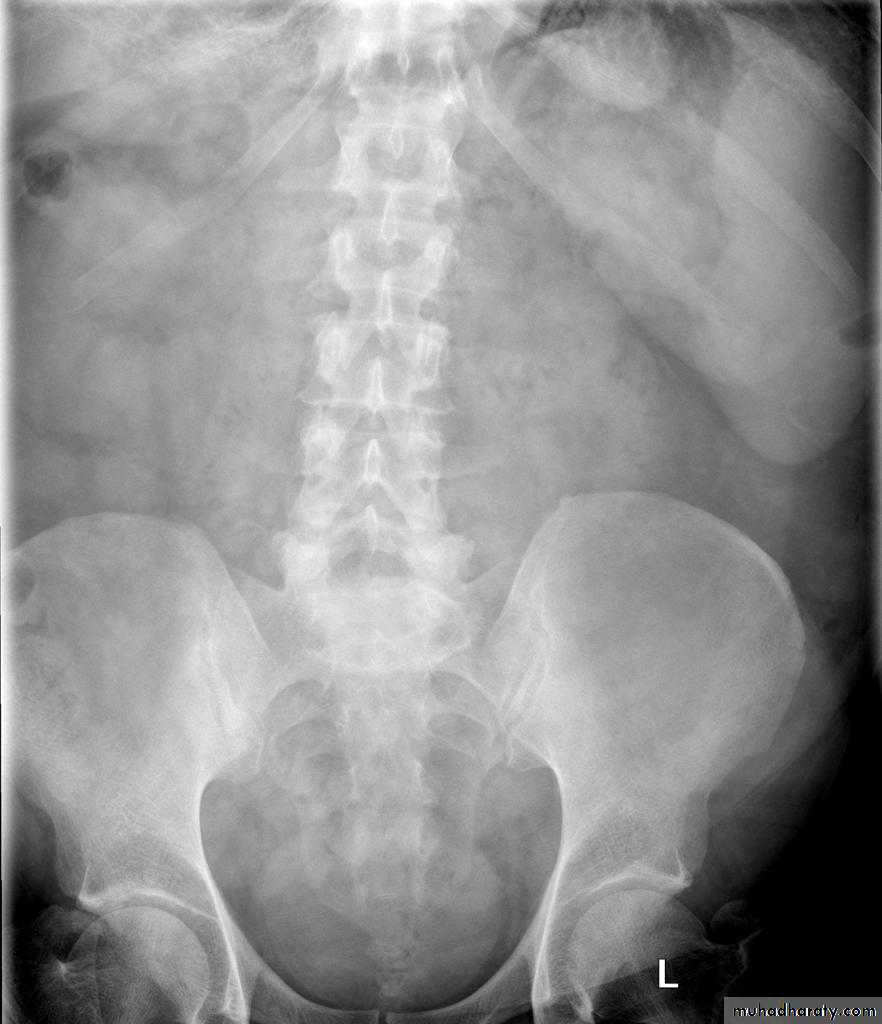

Ascites

Plain films are of very limited value in the diagnosis of ascites

Small amounts of ascites cannot be detected on plain films.

Larger quantities separate the loops of bowel and displace the ascending and descending colon from fat stripes. SB loops float to the center of abdomen

Ascites is more readily recognized with ultrasound or CT

Plain films of the liver and spleen

Substantial enlargement of the liver has to occur before it can be recognized on a plain abdominal film. As the liver enlarges it extended well below the costal margin displacing the hepatic flexure, transverse colon and right kidney downwards and displacing the stomach to the left .The diaphragm may also be elevatedOccasionly, there is a tongue-like extension of the right lobe into the right iliac fossa, this is a normal variant known as a "Reidl's lobe" and should not be confused with generalized liver enlargement.

As the spleen enlarges, the tip become visible in the left upper quadrant below the lower ribs. Eventually, it may fill the left side of the abdomen and even extend across the midline into the right lower quadrant. The splenic flexure and the left kidney are displaced downwards and medially , and the stomach is displaced to the right.